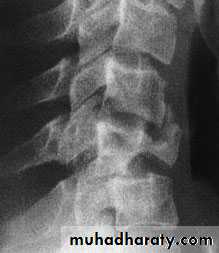

Lumbar Spine X Ray

Lateral radiograph

A/P radiograph• Sacrum